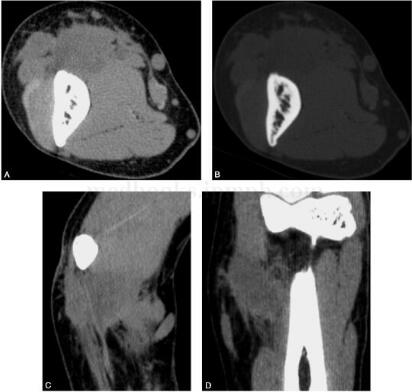

图2 CT:右肱骨下段邻近软组织内见直径约为2.2cm×1.8cm大小的软组织肿块影,边界不清,略低于肌肉密度,CT值约为36HU。邻近骨质未见异常